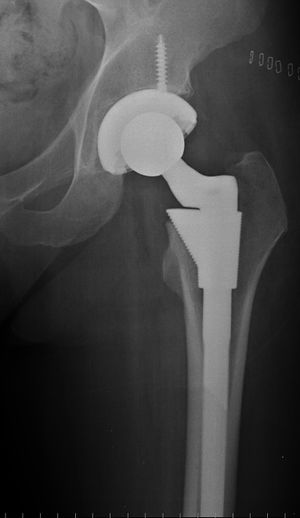

Cement free implant 16 days after surgery. Femoral component is cobalt chromium combined with titanium which induces bone growth into the implant. Ceramic head. Acetabular cup coated with bone growth inducing material and held temporarily in place with a single screw.